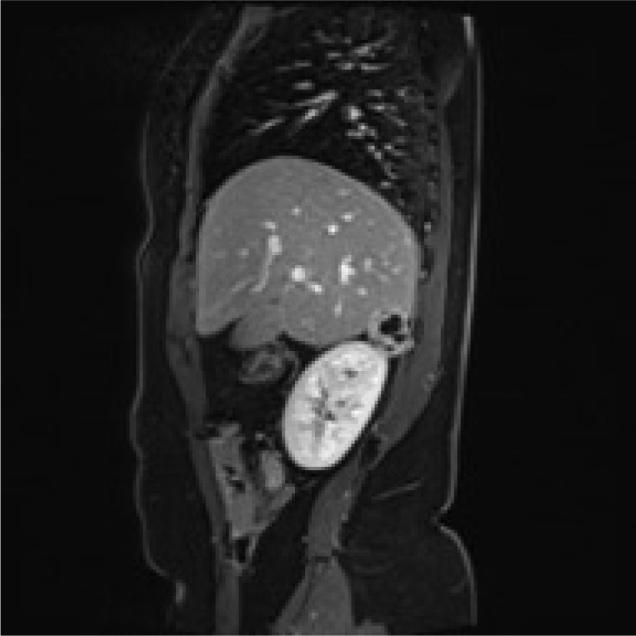

This is a 78-year-old Moroccan woman, with right flank pain for eight months previously. She denied contact with dogs or sheep. Her physical examination was normal. There was no pathological alteration of laboratory exams. CT scan measuring 5 cm without clear signs for a sure diagnosis found a round lesion in the right adrenal gland. An abdominal MRI showed a round mass of 34 x 27 mm with fluid component without a clear plane of dissection from kidney and liver. A laparoscopic procedure was performed to obtain a histological diagnosis. We reached a conclusive diagnosis of Hydatid cyst of right adrenal gland space. Hydatid cysts often develop in the liver. The location in the adrenal bed is rare without clinical signs related to alteration of the gland's secretion. Hydatid cyst identification in the adrenal gland space is based on ultrasonography, CT or MRI scans. The differential diagnosis includes various benign and malignant lesions. Laparoscopic procedure is the best approach available to obtain a histological diagnosis and a curative treatment. The best treatment for HD is the pericystectomy. Laparoscopic surgery can guarantee a radical resection of these lesions when it performed by an expert surgeon.

这是一名78岁的摩洛哥女性,此前右侧胁腹疼痛8个月。她否认与狗或羊有接触。体格检查正常。实验室检查无病理改变。CT扫描发现右侧肾上腺有一个5厘米的圆形病变,但没有明确的确诊迹象。腹部MRI显示一个34×27毫米的圆形肿块,有液体成分,与肾脏和肝脏没有清晰的分界平面。进行了腹腔镜手术以获得组织学诊断。我们最终确诊为右侧肾上腺间隙包虫囊肿。包虫囊肿常发生于肝脏。肾上腺床部位罕见,且无与腺体分泌改变相关的临床症状。肾上腺间隙包虫囊肿的诊断基于超声、CT或MRI扫描。鉴别诊断包括各种良性和恶性病变。腹腔镜手术是获得组织学诊断和根治性治疗的最佳方法。包虫病的最佳治疗方法是囊肿切除术。当由专业外科医生进行腹腔镜手术时,可以保证对这些病变进行根治性切除。